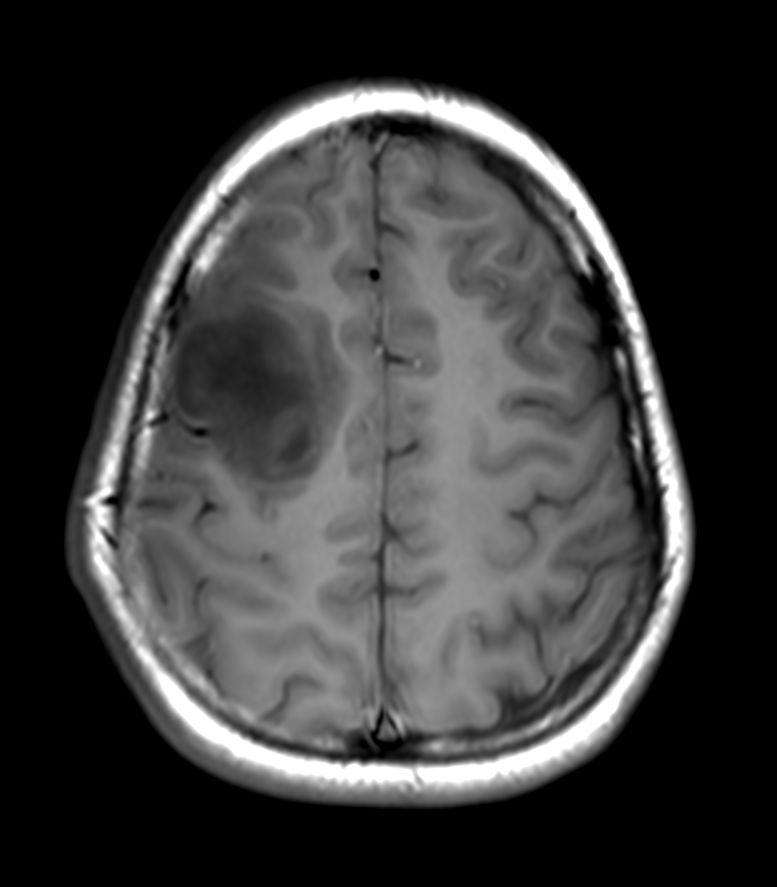

T1w SE

Diffusion (b1000)

Diffusion (ADC)